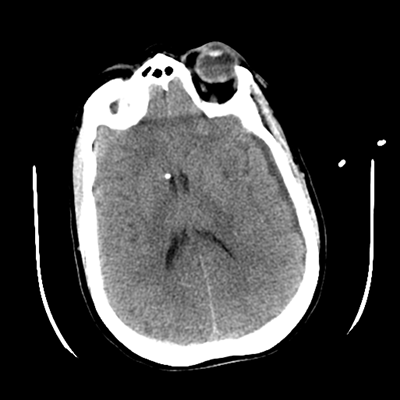

The patient goes down to CT. The following images are obtained. The subdural fluid collection is stable, as is the ventricular caliber.

NCHCT

Starting with the non-contrast head CT, we can appreciate that there's actually not much residual subarachnoid blood at all; it's essentially all resorbed already (and cleared through the EVD). The ventricular caliber is stable. With the CTA head (for convenience's sake, the MIPs were shown), it's subtle, but we can see that the PCAs on each side are not as smooth and regular. The right MCA, starting at the bifurcation, also becomes narrower. This is [radiographic] vasospasm. Now, looking at the CT perfusion-- specifically, the Tmax (MTT) map that were selected-- there's clearly some abnormality within the bilateral cerebellar hemispheres and occipital lobes. Not a lot, but it's there. Delving further into this map, we can appreciate that the areas of abnormality are mainly green, signifying that these areas have Tmax > 6 seconds. This is the threshold that is specific, not sensitive, for vasospasm.